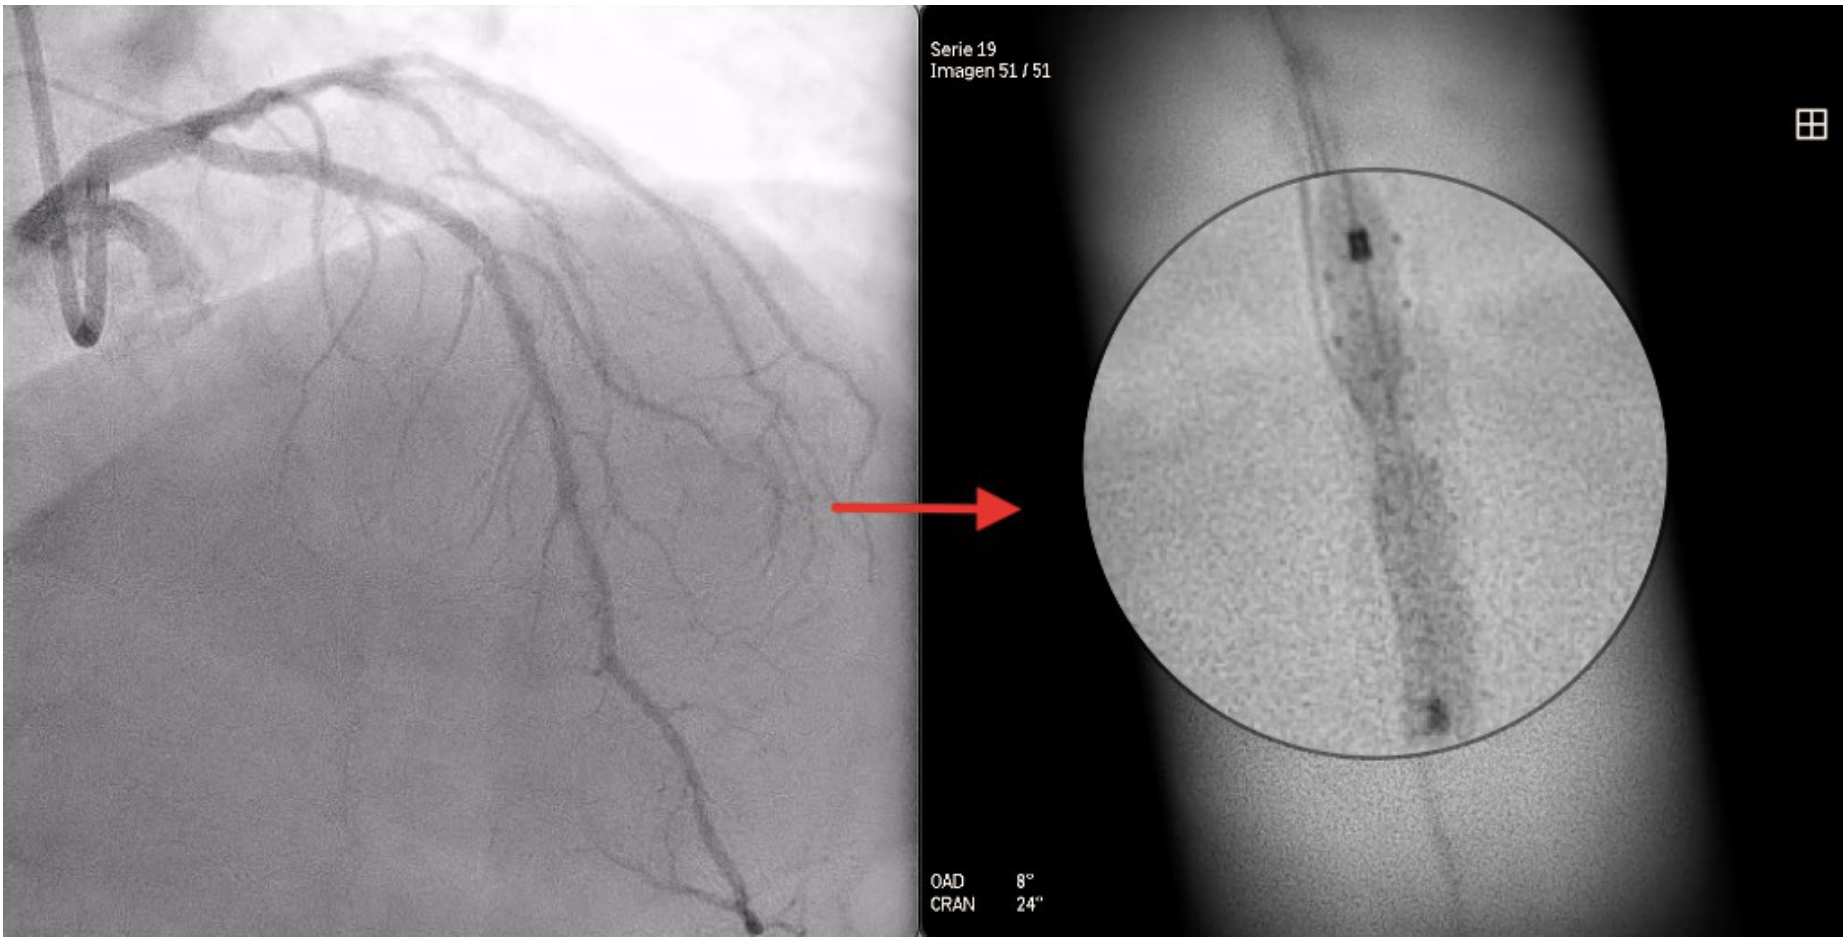

A 73-year-old man was hospitalized with acute coronary syndrome. Angiography showed severely calcified disease in the anterior descending artery and severe stenosis in the proximal, medial, and distal segments (Figure 1). Angioplasty was performed with an NC Trek Neo balloon (Abbott) with proper preparation of the plaque in the proximal and medial segments. Optical coherence tomography showed calcified plaque with a 360° ring and 1.2-mm thickness in the distal segment (Figure 2). Expansion attempts using a super high-pressure 2.5 x 10-mm OPN NC percutaneous transluminal coronary angioplasty (PTCA) balloon (SIS Medical) failed to fracture the calcification; rotational atherectomy with a Rotablator (Boston Scientific) was also unsuccessful. A 1.4-mm excimer laser coronary atherectomy catheter (Spectranetics) was also used (Figure 3) without fracturing the calcification, even after attempts with a super high-pressure balloon at 45 to 50 atm and being inflated for 40 to 60 seconds (Figure 4). Finally, a 3 x 28-mm Angiolite sirolimus-eluting stent (iVascular) was deployed in the proximal segments, followed by a 2.5 x 35-mm paclitaxel-eluting balloon (Medtronic) in the medial segment.